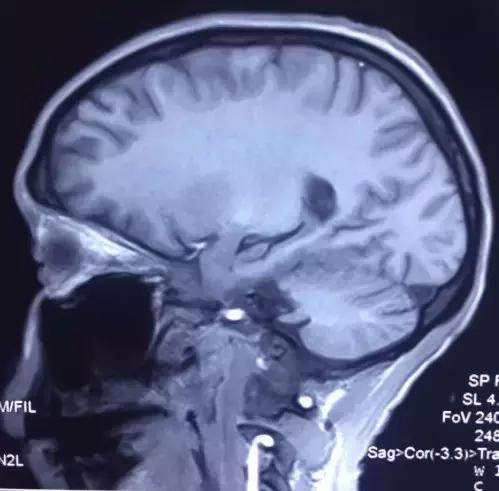

菅老师您好,打扰您了,今天下午做的磁共振,您看一下。

(部分图片)

核磁共振看的还可以,这个病人一点儿意识也没有吗?抽搐的话,脑电图对诊断应该有所帮助。